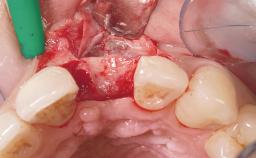

Immediate Flapless Placement of an Implant in a Maxillary Left Central Incisor Site

A 29-year-old female patient presented for treatment to replace the upper left central incisor tooth with an implant- supported restoration. The tooth had been intermittently symptomatic for the previous 12 months. The tooth had originally suffered trauma about 15 years previously. Several endodontic treatments had been performed, including an apicectomy procedure to retain the tooth. The patient was healthy and a non-smoker. She had reasonable expectations in regard to esthetic outcomes and the risk of marginal tissue recession following treatment. At medium smile, the gingival margins of the upper teeth were visible, with a display of 3 to 4 mm of the gingival margins. Gingival recession of tooth 21 and a discrepancy in the gingival levels between teeth 11 and 21 was observable during normal speech and smile.

| Placement Protocol | Immediate implant placement |

| Tooth Site | Maxillary incisor or canine |

| Socket Morphology | Single-root socket |

| Socket Integrity | Damage to one or more bone walls |